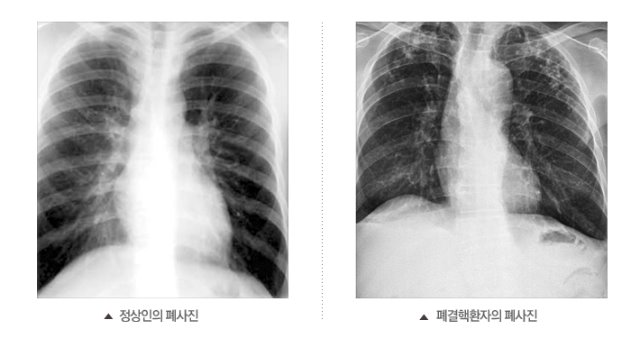

고양시는 국가결핵관리사업의 일환으로 2주 이상 기침이 지속되는 경우 보건소에서 결핵검사를 받아볼 것을 당부했다.

현재 국가결핵관리체계 구축을 통해 보건소를 중심으로 결핵환자 관리·치료, 집단시설 역학조사 등 여러 가지 사업이 진행되면서 결핵환자 발생이 감소하고 있지만 2017년 기준 인구 10만 명당 결핵 신환자 55명으로 아직도 OECD국가 중 결핵 후진국을 벗어나지 못하고 있는 실정이다.

특히 결핵은 결핵환자의 기침·재채기 등을 통해서 결핵균이 공기 중으로 배출되며 이를 주위 사람들이 들이마심으로써 감염될 수 있으므로 집단적인 결핵 발병을 막기 위해서는 조기 검진을 통하여 결핵을 진단받고 치료받는 것이 중요하다.